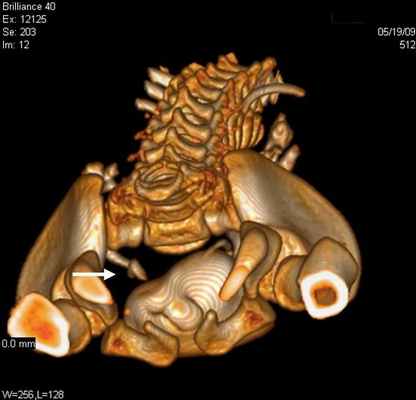

Болюсное введение контрастного вещества и последующее динамическое исследование различных фаз контрастирования способствует четкому выявлению уретероцеле (рис. 3б).

Уретероцеле обнаружено у 3 (8,1%) пациентов из 37. Этот порок уретеровезикального сегмента на МСКТ характеризовался с кистовидным расширением внутрипузырного сегмента мочеточника. При этом отчетливо определяется округлая полость, вдающаяся в просвет мочевого пузыря (рис. 3).

Рис 3. МСКТ картина уретероцеле. Трехмерная реконструкция. Удвоение почек и мочеточника справа (a) и уретероцеле слева (б)

Во всех наблюдениях устья мочеточников открывались в мочевой пузырь. В отличие от экскреторной урографии на МСКТ четко определяются изменения со стороны почек и мочеточника, особенно при трехмерной реконструкции.